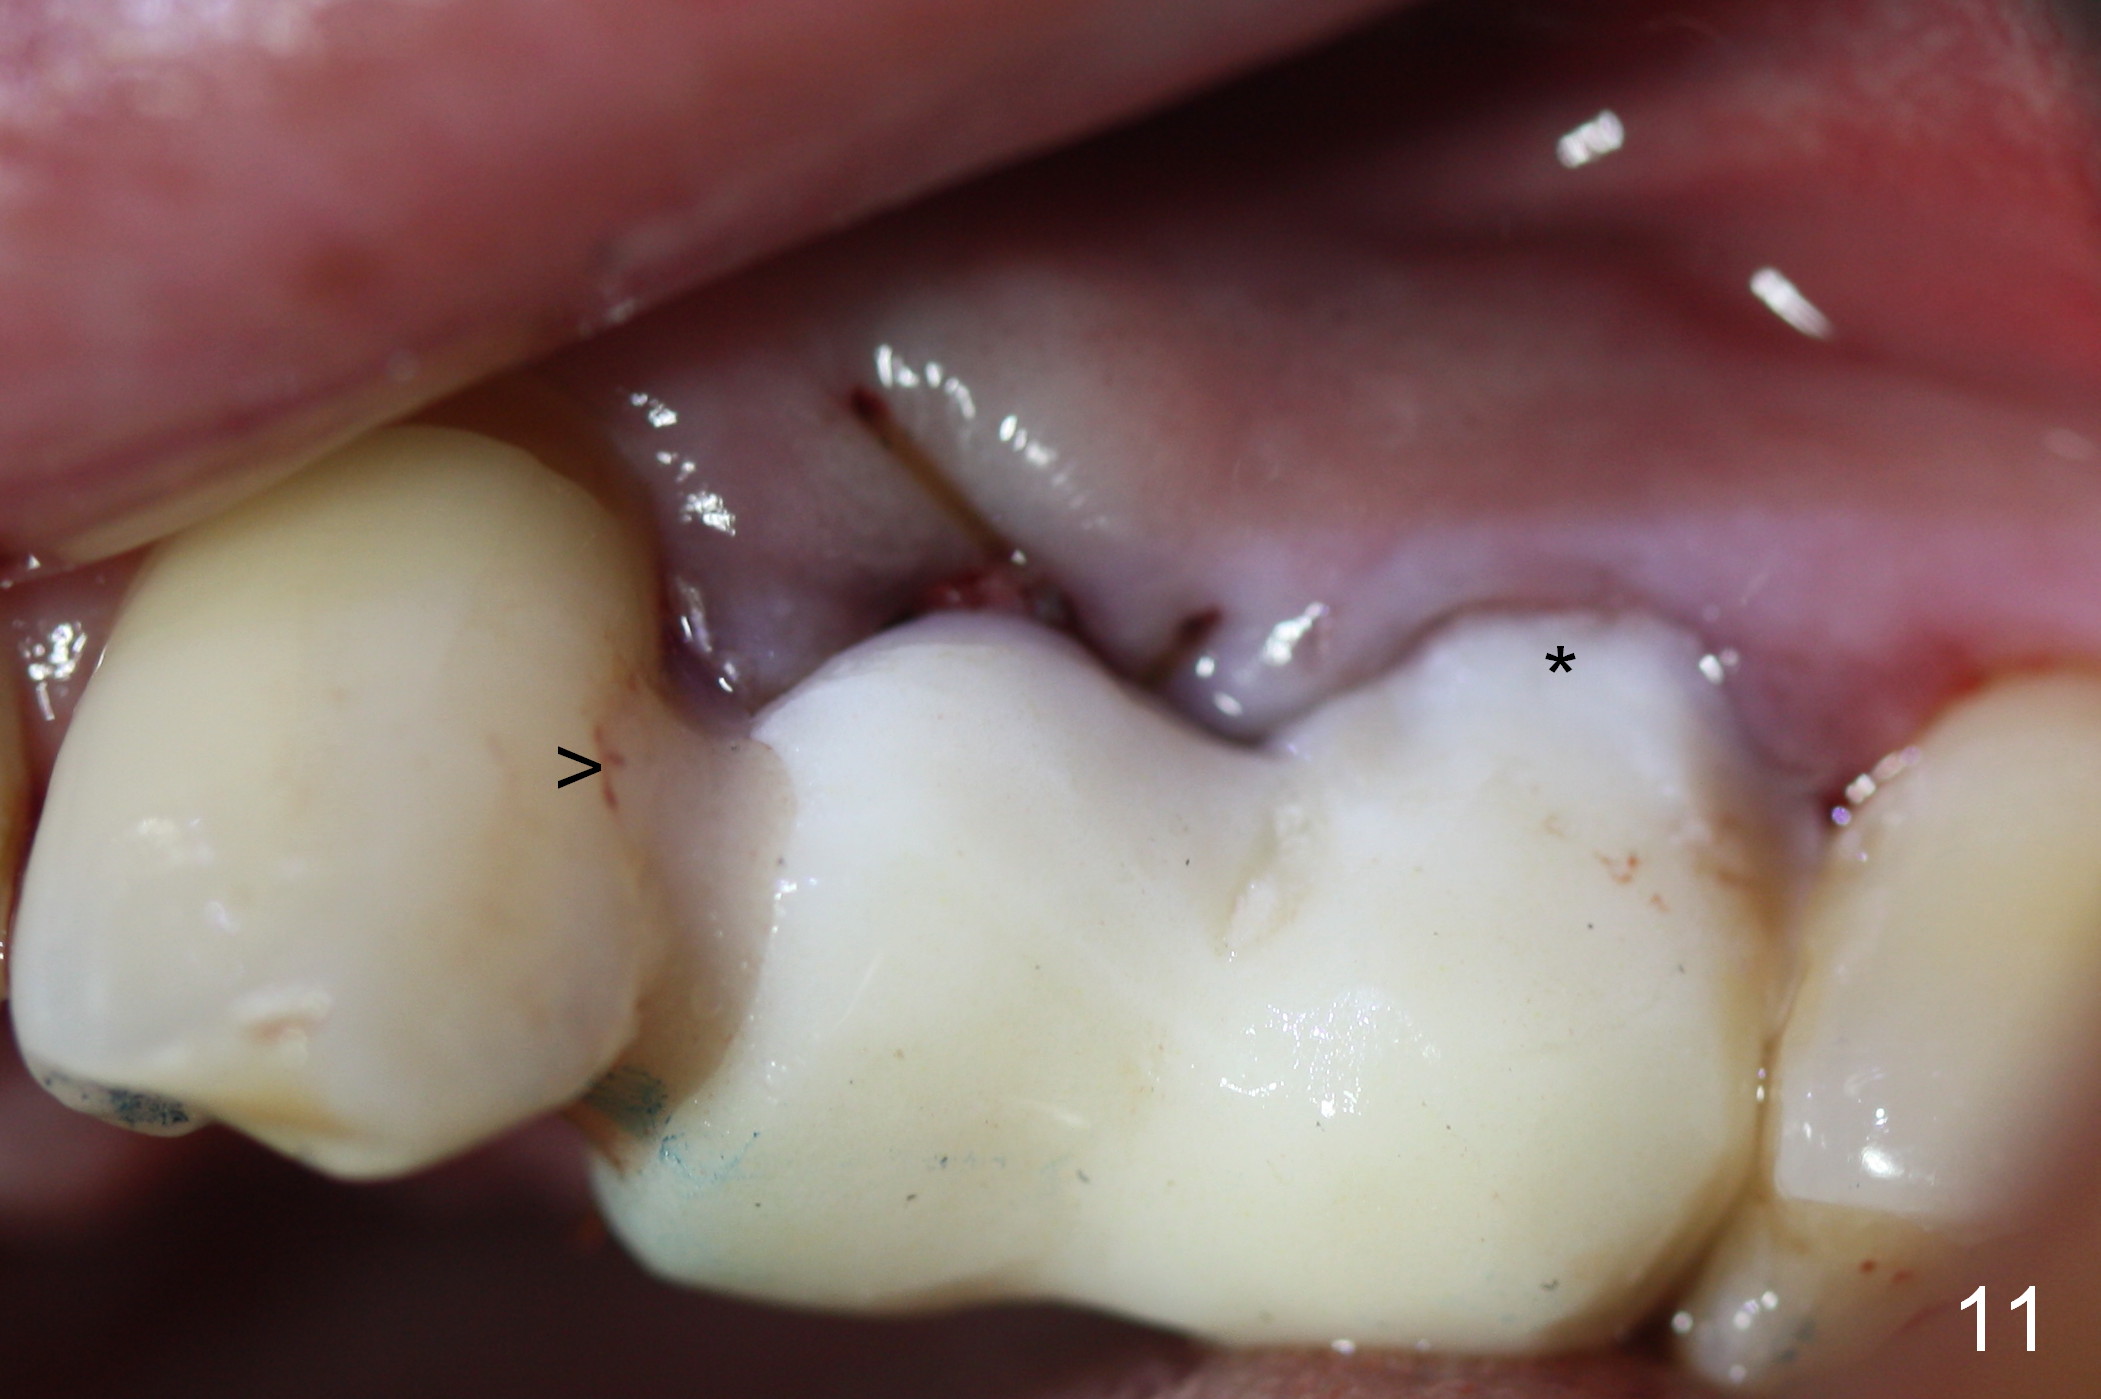

Taking 2 additional PAs with sensor 1 is frustrating (Fig.1,2), no apices shown. Osteotomy is done smoothly with 2 mm pilot drill at 20 mm, 2.5 mm reamer at 17 mm, and 3 mm reamer at 14 mm and 4.5x20 mm tap at 17 mm. The 1st intraop PA is taken with sensor 1 when 2 of 4.5x20 mm implants are placed (Fig.3); the implant at #12 is close to the root of the tooth #11. The 2nd PA is taken with sensor 2: the apex of #11 touches the implant at #12 (Fig.4). There is no separation when panoramic X-ray is taken (Fig.5). Effort is exerted to re-direct the osteotomy twice (Fig.6: tap; Fig.7: implant) without success. When the implant is removed, a PA is taken; it appears that the root of the tooth #11 has no damage (Fig.8). To obtain the best recovery, socket preservation is carried out with 50/50 cortical/cancellous allograft mixed with Osteogen (Fig.12 *) and Collagen Dressing (Fig.9: #12). A 2 (or 3)-unit provisional bridge (Fig.10: #12,13) is fabricated over the implant (Fig.9 I)/abutment (A) to cover these 2 sockets. After acid etching #11 D surface (Fig.9 >) and relining (Fig.11 *), the provisional bridge is bonded to the tooth #11 (Fig.11,12 black >) so that bone graft will be less likely dislodged.